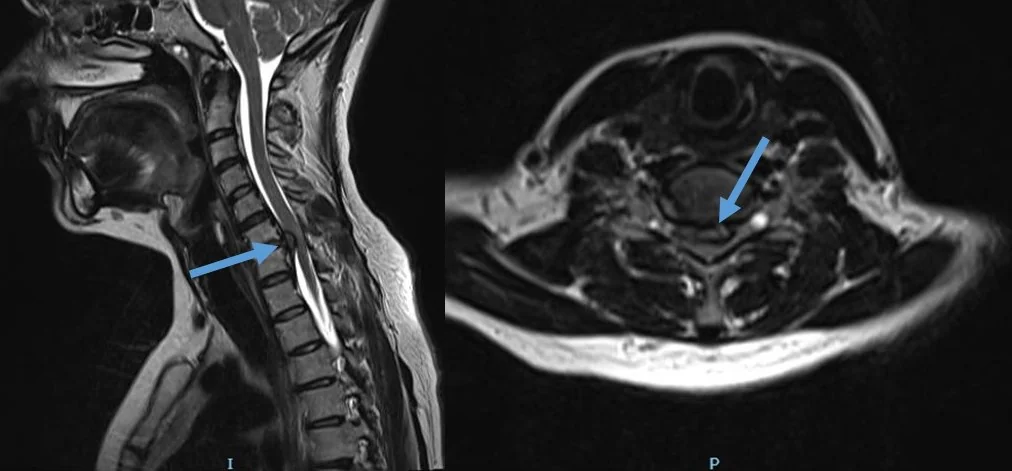

A mielopatia cervical ocorre quando a hérnia de disco ou a degeneração da coluna comprime a medula espinhal — e não apenas as raízes nervosas. Essa é uma condição mais séria e exige atenção imediata.

A mielopatia cervical é progressiva. Quanto mais tempo a medula fica comprimida, maiores as chances de dano permanente. Por isso, quando esse quadro é identificado, a cirurgia costuma ser indicada com urgência.

O diagnóstico é feito com ressonância magnética, que mostra o grau de compressão e se há sinal de lesão medular.

- Ressonância Magnética (RM) da coluna cervical: exame principal para avaliar o disco, as raízes nervosas e a medula espinhal. Mostra o grau e a localização da compressão.

Indicada principalmente nos casos de mielopatia cervical com compressão em múltiplos níveis. O procedimento amplia o canal vertebral para descomprimir a medula espinhal.